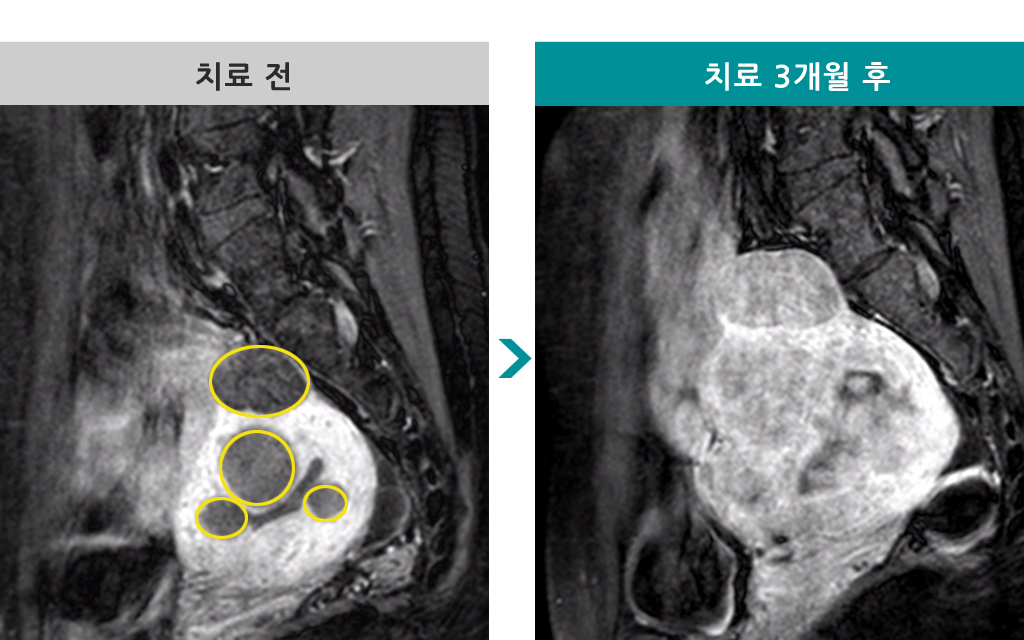

49세 [자궁선근증 색전술] 전후 MRI사진 비교